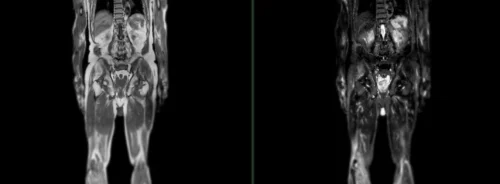

Breast cancer is treatable when detected early, but finding cancers early enough has been a significant challenge for standard mammography which miss about 30% of cancers. The KBCT addresses this gap by offering NO-COMPRESSION, TRUE 3D Breast CT technology, vastly improving the detection of breast cancer. The device's ability to detect cancers as early as stage 0 and stage 1 and identify lesions as small as 2mm and calcifications as small as 200 microns represents a significant leap forward in early cancer detection.

At the recent RSNA, Koning had the great opportunity of showcasing their device at the Swissray booth - Swissray has recently signed on as one of Koning's distributor partners. The booth attracted a substantial number of visitors, including clinicians, researchers, and healthcare professionals, eager to learn about the transformative potential of the KBCT. The device's sensitivity coupled with its ability to take the place of multiple imaging applications (i.e. biopsy, contrast enhancement, and an alternative for breast MRI imaging) garnered significant interest. It is clear that Koning continues to maintain its leading technological and regulatory advantage versus competitors who were also present at RSNA.